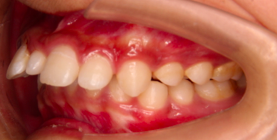

前牙反颌

“地包天”又称前牙反颌,是较为常见的牙齿颌面畸形,前牙反颌的患者外观形象大打折扣,同时咀嚼功能大幅度降低,其表现通俗来讲就是下前牙位于上前牙的外侧。